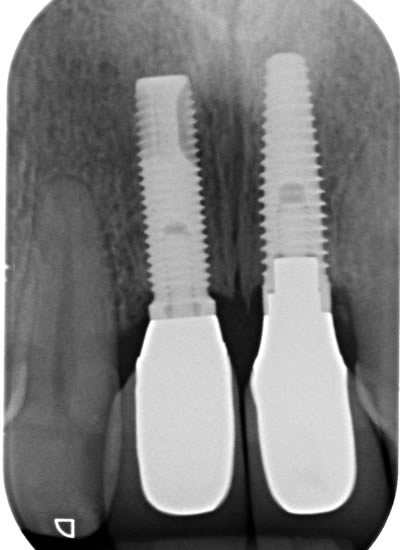

More front teeth replaced by dental implants

Case Three (4 images)